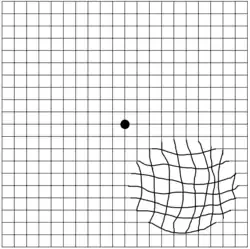

Metamorphopsia (from Ancient Greek: μεταμορφοψία, metamorphopsia, 'seeing mutated shapes') is a type of distorted vision in which a grid of straight lines appears wavy or partially blank. In addition, metamorphopsia can result in misperceptions of an object's size, shape,[3] or distance to the viewer. People can first notice they suffer from the condition when looking at mini blinds in their home.

Tests used for diagnosis of metamorphopsia mostly make use of subjective assessments of how a person views regular patterns. Many of these tests have a poor ability to accurately diagnose or identify a person with the disease (i.e.,poor sensitivity).[8] The use of tests such as the preferential hyperacuity perimetry, a psychophysical test that assesses misalignments of visual objects, may permit a more sensitive diagnosis of metamorphopsia.[8]